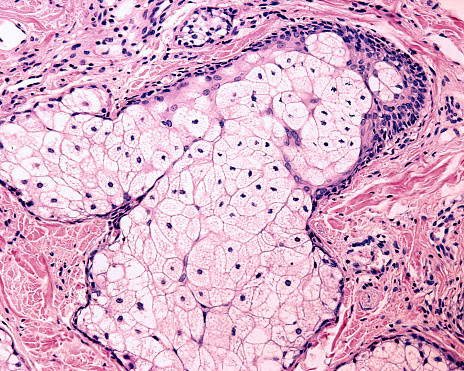

Сальные железы: простые и альвеолярные